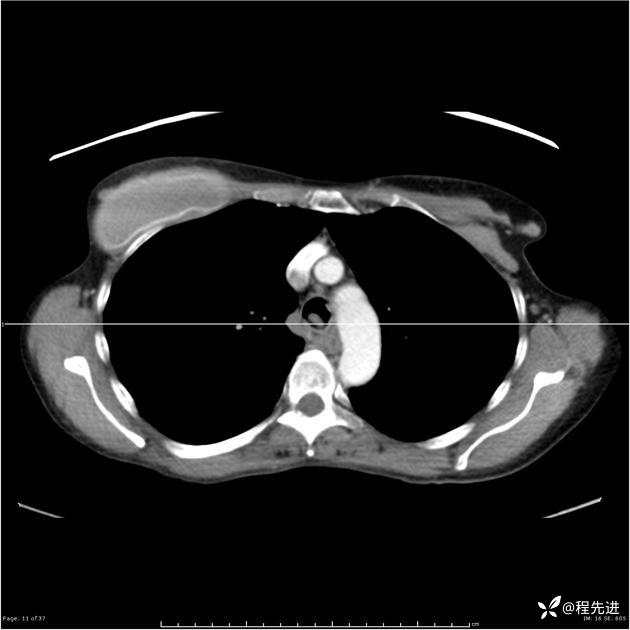

病例女,53岁,气管、左主支气管、下叶支气管内结节,乳头状瘤?期待你的精彩解读

女,53岁

乳头状瘤?